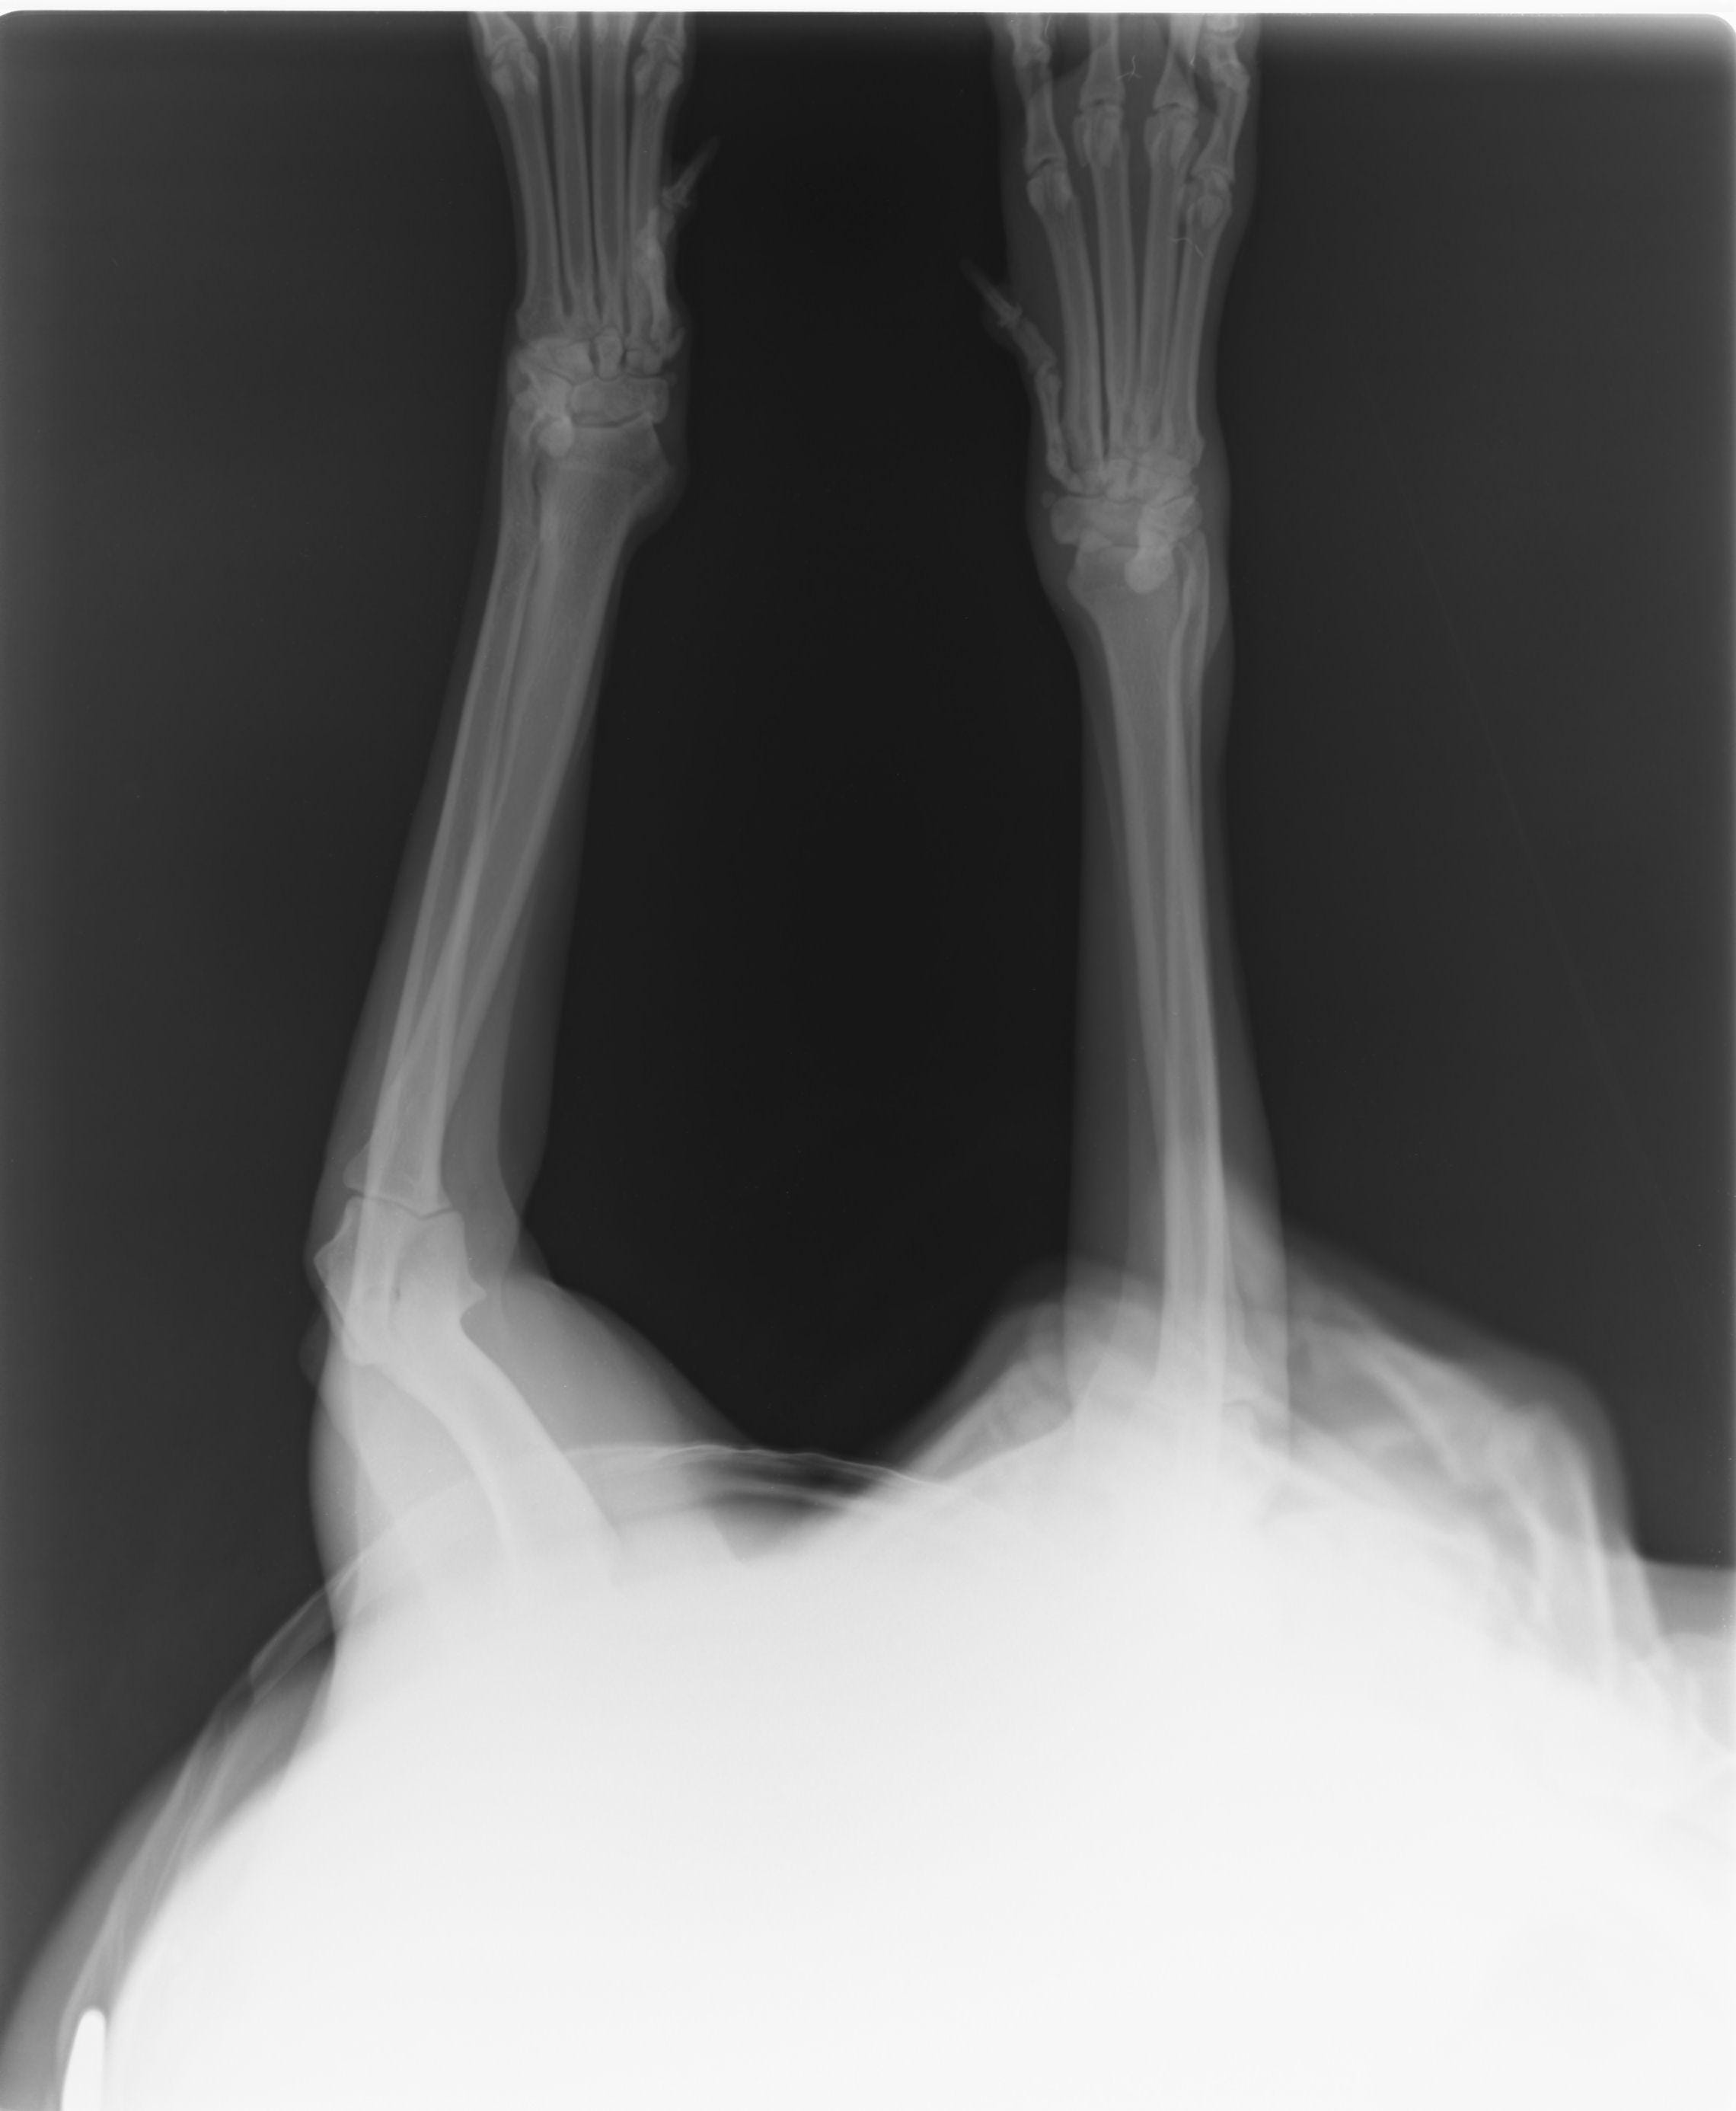

Hi. I live in lebanon and my belgian malinois has hurt her right wrist. I took her to the the 1st vet and he said that the swelling will go away and there was no fracture. I wasnt convinced so i took her to a 2nd vet who said that that there is fracture and he put a cast on her leg. Without a cast she shows signs of carpal hyperextension, but the vet said it isnt the case. From the xray images does it show a fracture, and if it does does it produce symptons of carpal hyperextension? Thanks a lot

It does look like there is fracture on the last phalang of what i assume is the right wrist (it's not indicated on the xray so can't know 100%), i cannot tell if it is causing symptoms of hyperextension from the xray but it was in my opinion the right decision to cast it for it to heal better.